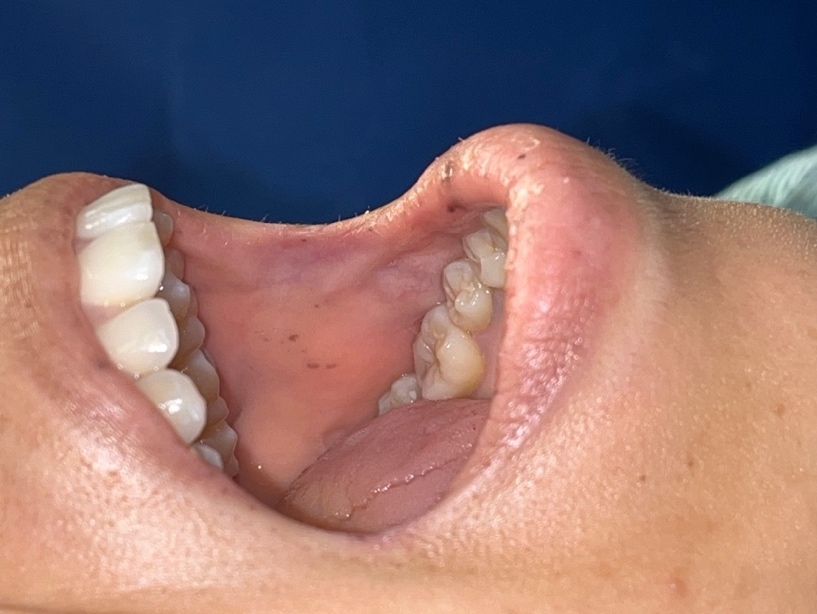

A 29-year-old woman with a past medical history of severe anemia and lactose intolerance presented to the emergency department with complaints of nausea, vomiting, non-bloody diarrhea, and intermittent diffuse abdominal pain for 5 days following the intake of food with cheese. She denied fever, chills, hematuria, hematochezia, melena, or a history of heavy menstrual bleeding. She took ibuprofen 2-3 times every month for chronic headaches and iron supplements one year before presentation for severe anemia. However, she did not have any previous records or workup available for her anemia, except for a complete blood count from a year back showing a hemoglobin level of 6.0 g/dL and low MCV. She was a Jehovah’s Witness and, as per her religious beliefs, she declined blood transfusions. At presentation, she was afebrile, with a blood pressure of 134/78 mmHg, pulse rate of 89/min, and was maintaining normal saturation on ambient air. Physical examination showed severely pale mucosa and hyperpigmented lesions on the buccal mucosa (Figure 1). Laboratory evaluation showed severe iron deficiency anemia with a hemoglobin of 4.8 g/dL, MCV 64fL, serum iron of 12 mcg/dL, TIBC 423 mcg/dL, transferrin saturation of 2.8%, LDH of 238 IU/L, and ferritin of 2.27 ng/mL.

Peutz-Jeghers syndrome (PJS) is a rare autosomal dominant inherited disorder, but may occur sporadically in up to 30% cases, as in our patient, with no prior family history.3 It has an estimated incidence ranging between 1 in 8,300 and 1 in 200,000 individuals.3 Despite autosomal dominance, it may have variable penetrance, leading to clinical heterogeneity and a challenge in diagnosis. A clinical diagnosis of PJS is made when any one of the following is present: (i) two or more histologically confirmed PJS polyps, (ii) any number of PJS polyps with a family history of PJS in a close relative, (iii) characteristic mucocutaneous pigmentation with a family history of PJS, or (iv) any number of PJS polyps with characteristic mucocutaneous pigmentation.4 94% of those with a clinical diagnosis have a culprit mutation in the serine-threonine kinase 11 (STK11/LKB1) tumor suppressor gene located on chromosome 19.4 This mutation leads to dysregulated growth, forming hamartomatous polyps, and increasing the risk of malignancy.1 Our patient had more than two histologically confirmed hamartomatous polyps, characteristic mucocutaneous pigmentation, and a mutation in the STK11 gene, confirming the diagnosis of PJS. The mucocutaneous pigmented lesions seen in 95% of patients with PJS commonly occur in the lips, buccal mucosa, peri-anal region, hands, and feet.4 Polyps of varying sizes and numbers most commonly involve the small intestine (60-90%), but may also be present in the colon (50-64%), stomach (49%), and the rectum (32%).1,4 Polyps have also been reported at extraintestinal sites like the gallbladder, bronchi, bladder, and ureter.4 These polyps lead to various complications, including intussusception and small bowel obstruction, chronic occult gastrointestinal bleeding causing severe iron deficiency anemia, as in our case, or malignant transformation.